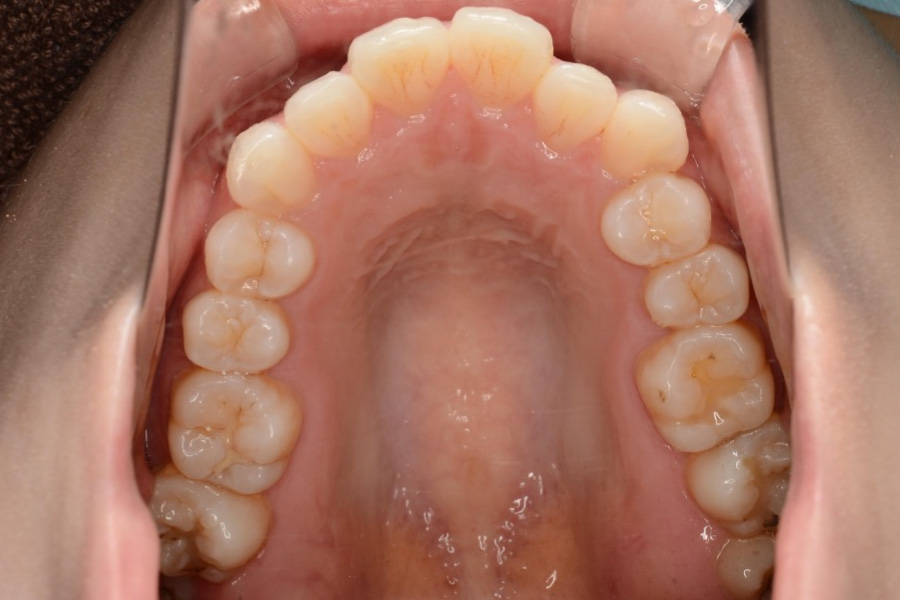

治療前

主訴 下の歯のガタつき、前歯の突出感が気になる

治療内容 インビザライン矯正

非抜歯